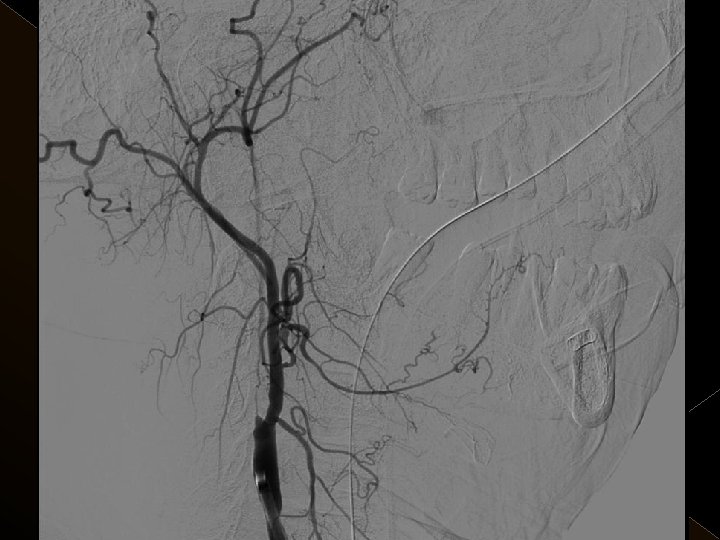

� 25 hasta (16 K, 9 E) , 27 vaskuler okluzyon � 16 orta serebral arter (MCA), � 6 baziler arter ve � 5 internal karotis arter (İCA) düzeyinde olmak üzere � Toplam 25 hasta, 27 tıkanıklığa (6 sı hariç) iv tpa sonrası endovaskuler yolla müdahale edildi

Uygulama � Toplam trombolitik ajan dozu: 0. 9 mg/kg , 0. 3 mg/kg’ lık bölümü intraarteriel işlemde � Tpa uygulaması sonrası 24 saat boyunca ek antikoagulan uygulanmadı. � İşlem sonrası kan şeker değeri 120 mg/lt de tutulmaya çalışıldı. � Endovasküler işlem sonrası KB tedrici düşme. KB 180/100 mm/Hg’nin üzerine çıkmadıkça müdahale edilmedi.

� İnme tedavisinde iv tpa uygulamasını takiben � intraarteriyel (İA) trombolitik tedavi (ia tpa ve ia mekanik trombolizis) � İA stent yardımı ile trombektomi yöntemleri kullanılarak tedaviye cevap ve komplikasyonlar araştırıldı.